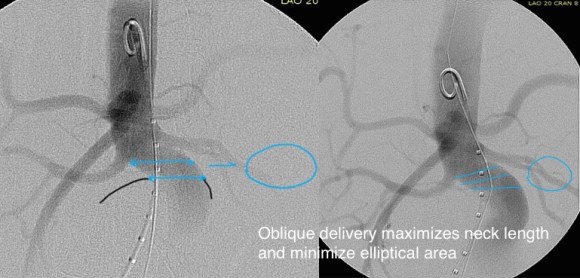

2. EVAR -This is outside the IFU for any of the available devices because of the highly tortuous neck anatomy. While note shown, the external iliac arteries were 5mm in diameter, but in the absence of plaque, was possibly due to spasm. The Nellix device is yet on trial, but there are limits on how much you can straighten this neck. The devices with suprarenal stents end up straightening out the graft with deployment of the graft in an ellipse. This also means loss of seal zone length which decreases with oblique deployment. FEVAR is not possible because of this neck tortuosity as well but was considered briefly.

I tried two things that was different. I felt that a stiff wire would result in horizontal orientation of the top of the graft, and so I placed a bend in the wire. Prior experience with unintended bends in wires have taught me that passing these wires is largely tolerated as long as it is done through catheters and sheaths. The other thing I did was bend the top of the delivery system -this was done with some care as I did not want to detach the contraining mechanism.

The wire and delivery system modification did tilt the top of the graft away from the left side of the aorta. It had the unintended effect of keeping the wall grabbing anchors away from the near wall while constrained.

It didn’t tilt the graft as much as I would have liked, but the graft deployed in a left to right fashion that allowed for controlled delivery across all of the available neck. Gratifyingly there was seal (below). I flared the right, while excluding the left iliac bifurcation because of the larger iliac aneurysm.